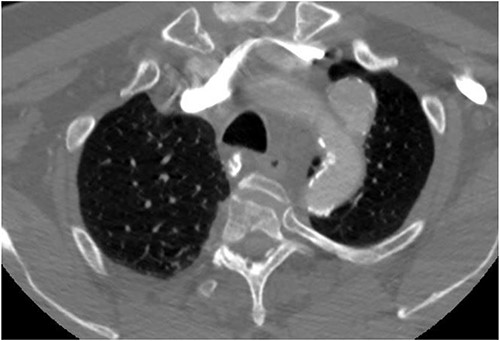

The patient is a 70-year-old male with an incidental finding of a proximal LSA aneurysm on computed tomography (CT) angiography of the chest performed for shortness of breath. He had no dysphagia, neurologic or vascular occlusive symptoms. He had no history of trauma or known congenital anomaly. The aneurysm had a maximal diameter of 3.4 cm and was located at the origin of the artery (Fig. 1). An aberrant left vertebral artery and hypoplastic right vertebral artery were also identified. The left vertebral artery originated from the aortic arch proximal to the LSA takeoff (Fig. 2) and provided dominant posterior cerebral circulation.

Preoperative CTA demonstrating LSA aneurysm; located at the origin from the aortic arch.